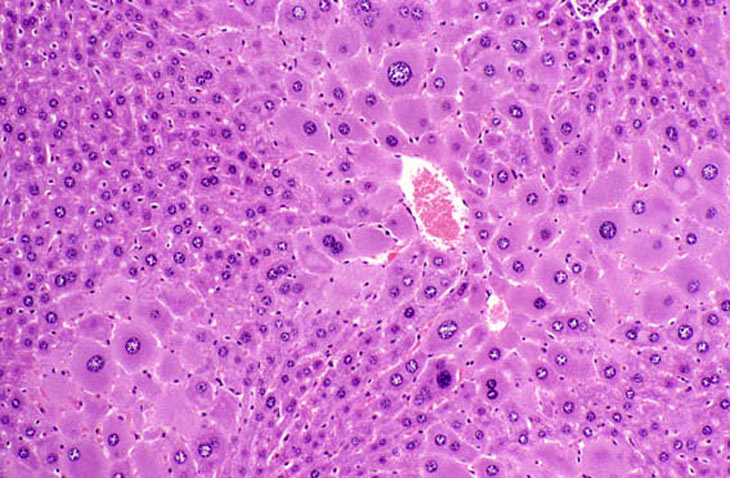

Minimal centrilobular hepatocyte hypertrophy is present and most dramatically involves enlargement of hepatocytes immediately adjacent to the central vein. The periportal hepatocytes (right side of image) are not affected.